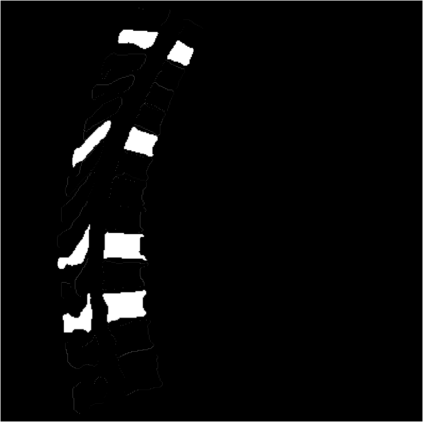

Vertebrae localization, segmentation and identification in CT images is key to numerous clinical applications. While deep learning strategies have brought to this field significant improvements over recent years, transitional and pathological vertebrae are still plaguing most existing approaches as a consequence of their poor representation in training datasets. Alternatively, proposed non-learning based methods take benefit of prior knowledge to handle such particular cases. In this work we propose to combine both strategies. To this purpose we introduce an iterative cycle in which individual vertebrae are recursively localized, segmented and identified using deep-networks, while anatomic consistency is enforced using statistical priors. In this strategy, the transitional vertebrae identification is handled by encoding their configurations in a graphical model that aggregates local deep-network predictions into an anatomically consistent final result. Our approach achieves state-of-the-art results on the VerSe20 challenge benchmark, and outperforms all methods on transitional vertebrae as well as the generalization to the VerSe19 challenge benchmark. Furthermore, our method can detect and report inconsistent spine regions that do not satisfy the anatomic consistency priors. Our code and model are openly available for research purposes.